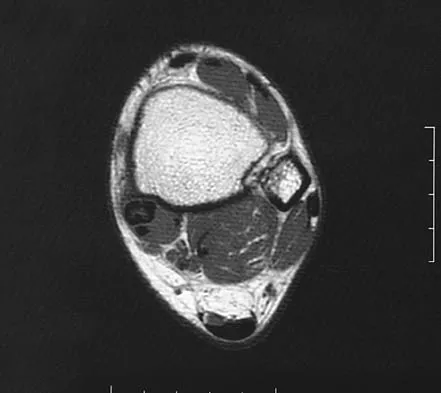

A 47-year-old man has acute right shoulder pain after falling off a ladder. The MRI scan shown in Figure 9 reveals

Correct Answer: a full-thickness rotator cuff tear.

The MRI scan reveals a full-thickness rotator cuff tear with retraction and increased signal in the subacromial space indicating joint fluid. Herzog RJ: Magnetic resonance imaging of the shoulder. Instr Course Lect 1998;47:3-20.